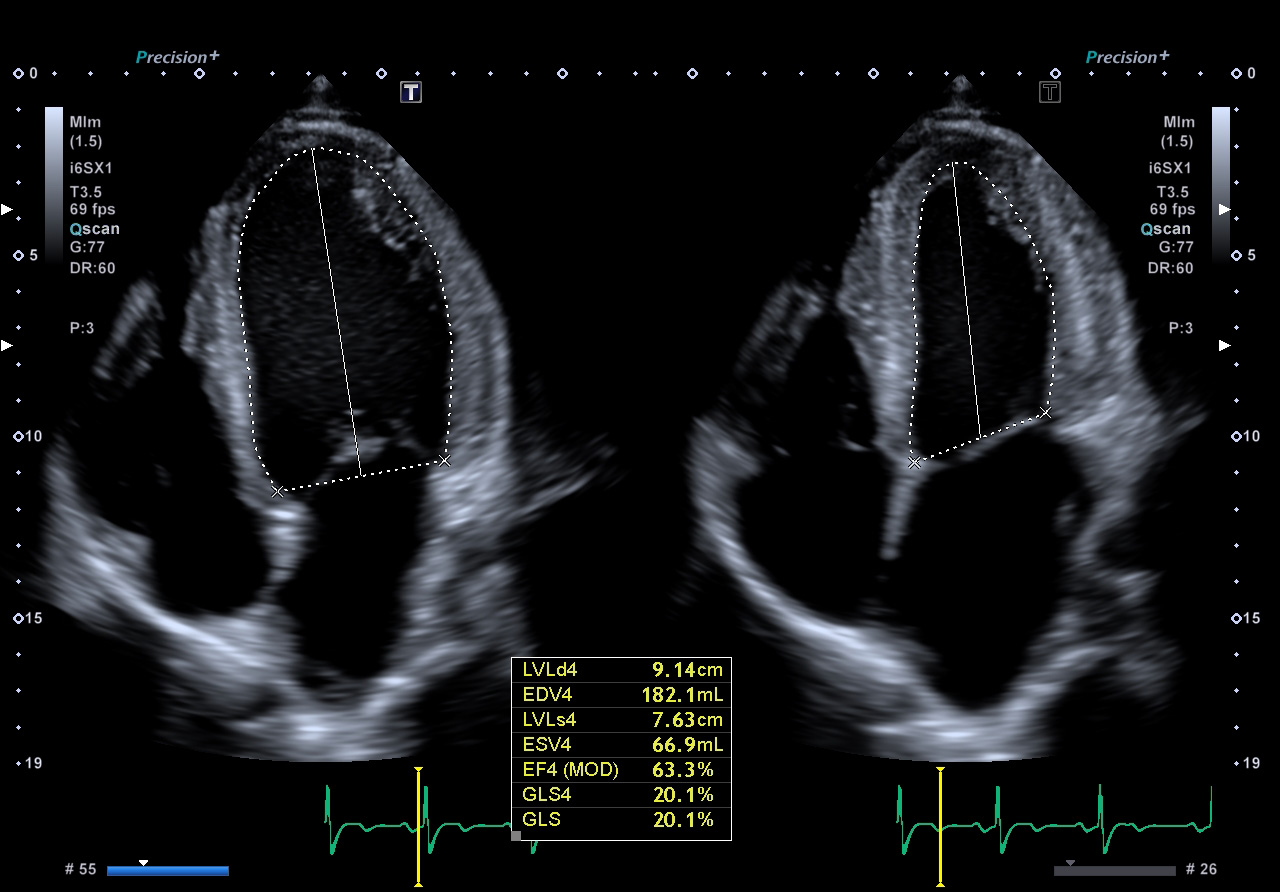

Auto-EF with Global Longitudinal Strain (GLS)1

- Automatic integration of Strain measurements with Ejection Fraction and volume measurements

- No need to enter dedicated strain packages

- Aplio systems automatically calculate Ejection Fraction, LV volumes and now GLS.

- Auto EF with Full-assist function is powered by artificial intelligence2

1Available on Aplio i-series / Prism Edition and a-series

2Available on Aplio i-series / Prism Edition

Automatic integration of Strain measurements with Ejection Fraction and volume measurements without the need of dedicated strain packages.

- 2D Wall Motion Tracking with Full-assist function features a seamless workflow by introducing artificial intelligence-based, machine learning technology for tracing the endocardial border.*

- No need for lengthy offline analysis. Everything at the bedside seamlessly.

- Aplio CV systems automatically calculate Ejection Fraction, LV volumes and other important parameters.

*Available on Aplio i-series / Prism Edition